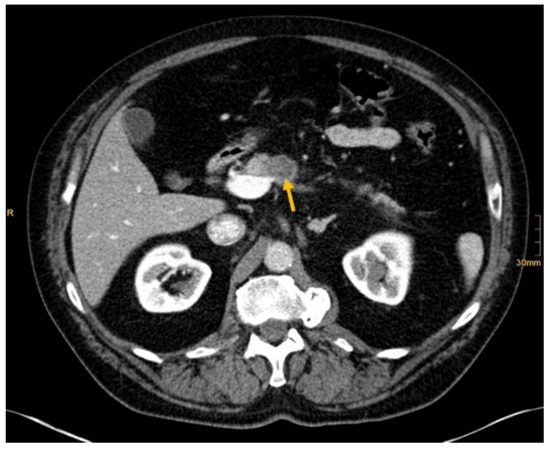

Figure 2. Pancreatic cancer (arrow). Correctly identified by one radiologist without and by all three radiologists with given clinical information (Conspicuous pancreas lesion seen in abdominal ultrasound. Laryngeal carcinoma several years ago.).

There are several reasons why tumors and metastases could be missed by radiologists. Firstly, the interpretation of oncological CT data sets is challenging; often multiple abnormalities are present in a single patient. Lesions may be benign and not always malignant. Therefore, findings could be undercalled and misinterpreted as benign (e.g., Figure 2) [1]. Findings may also be too small to be classified as malignant or may be overlooked (e.g., Figure 4). Additionally, findings, particularly of the lung, could be consistent with a postinflammatory benign aetiology due to configuration and subpleural location (e.g., Figure 5) [46]. Secondly, the so-called satisfaction of search represents another possible influence on the detection rate of malignant lesions. Satisfaction of search represents an interference of a radiological finding with the detection of further abnormalities [1,47]. Radiological image interpretation often follows a fixed procedure. Thus, as soon as a finding (mostly the primary tumor) is made, further lesions as metastases may be missed. This may explain the lower rate of true positive metastatic findings. Further reasons for missed metastatic lesions can be assumed. Metastases are often small, not reliably distinguishable from benign lesions and therefore an unequivocal diagnosis is often impossible without follow-up imaging or complementary procedures such as MRI, hybrid imaging, or biopsy. Moreover, imaging criteria for lymphogenous metastases are often controversial, an accurate identification is challenging. In the past, a short axis diameter of 1 cm was used as the cut-off value for enlarged, malignancy-susceptible lymph nodes [1]. Recent studies suggest different parameters for various anatomic regions, such as 6 mm for retrocrural or 8–10 mm for pelvic lymph nodes. However, enlarged lymph nodes are not always malignant. They also could have an inflammatory aetiology or normal-sized lymph nodes may have tumor involvement [48]. Of course, there are numerous cases in the present study that had been solved correctly. Figure 3 shows an example of a pancreatic carcinoma correctly diagnosed by all three radiologists irrespective of clinical information.